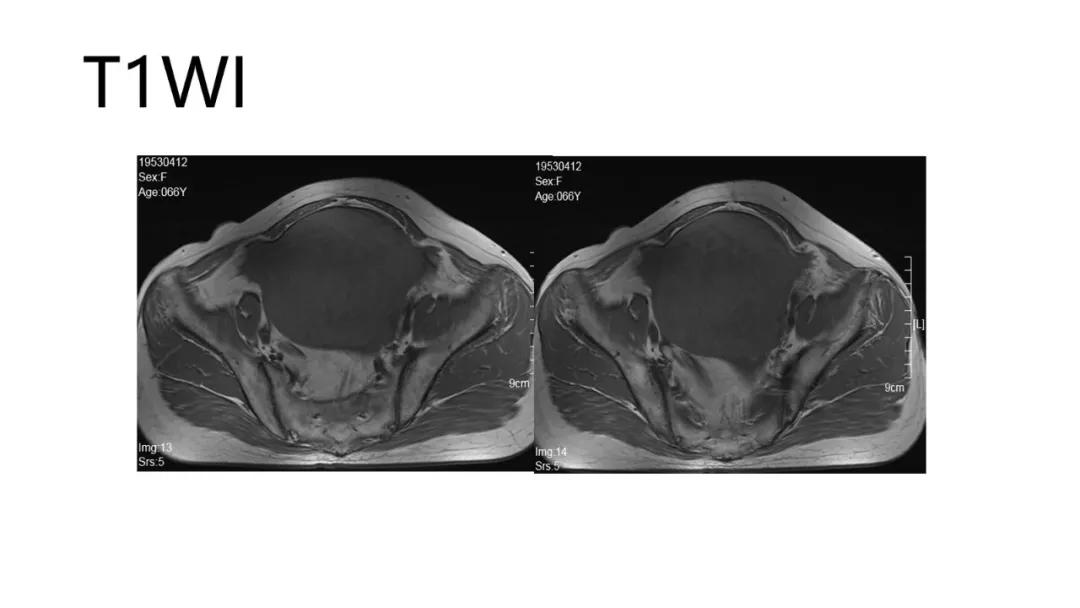

病理:左侧卵巢卵泡膜-纤维瘤